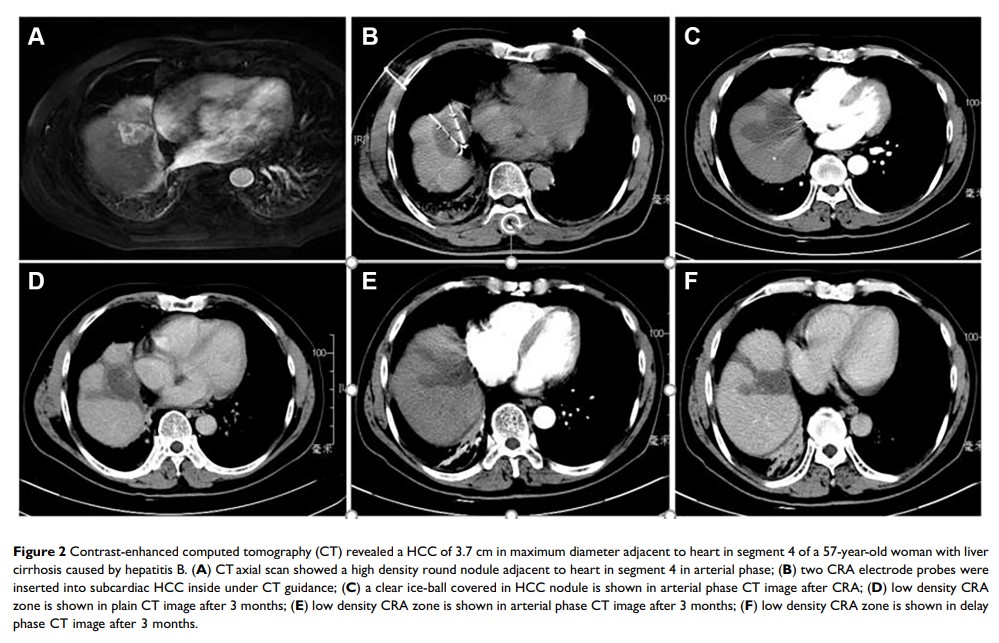

计算机断层扫描引导的经皮冷冻消融治疗心下(Subcardiac) 肝细胞癌:安全性、疗效、治疗效果和生存结果的危险因素